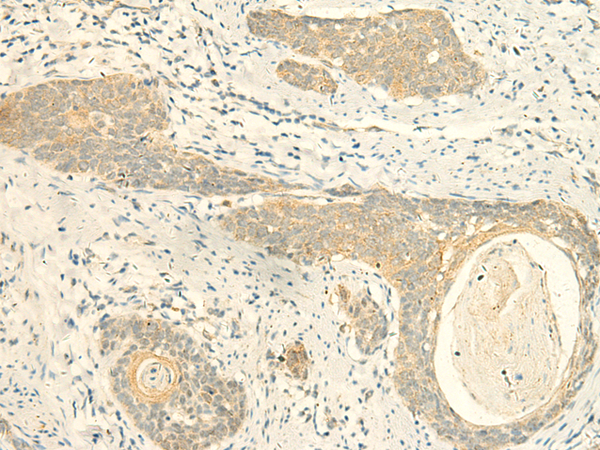

IHC positive control: |

Human esophagus cancer |

IHC Recommend dilution: |

40-200 |